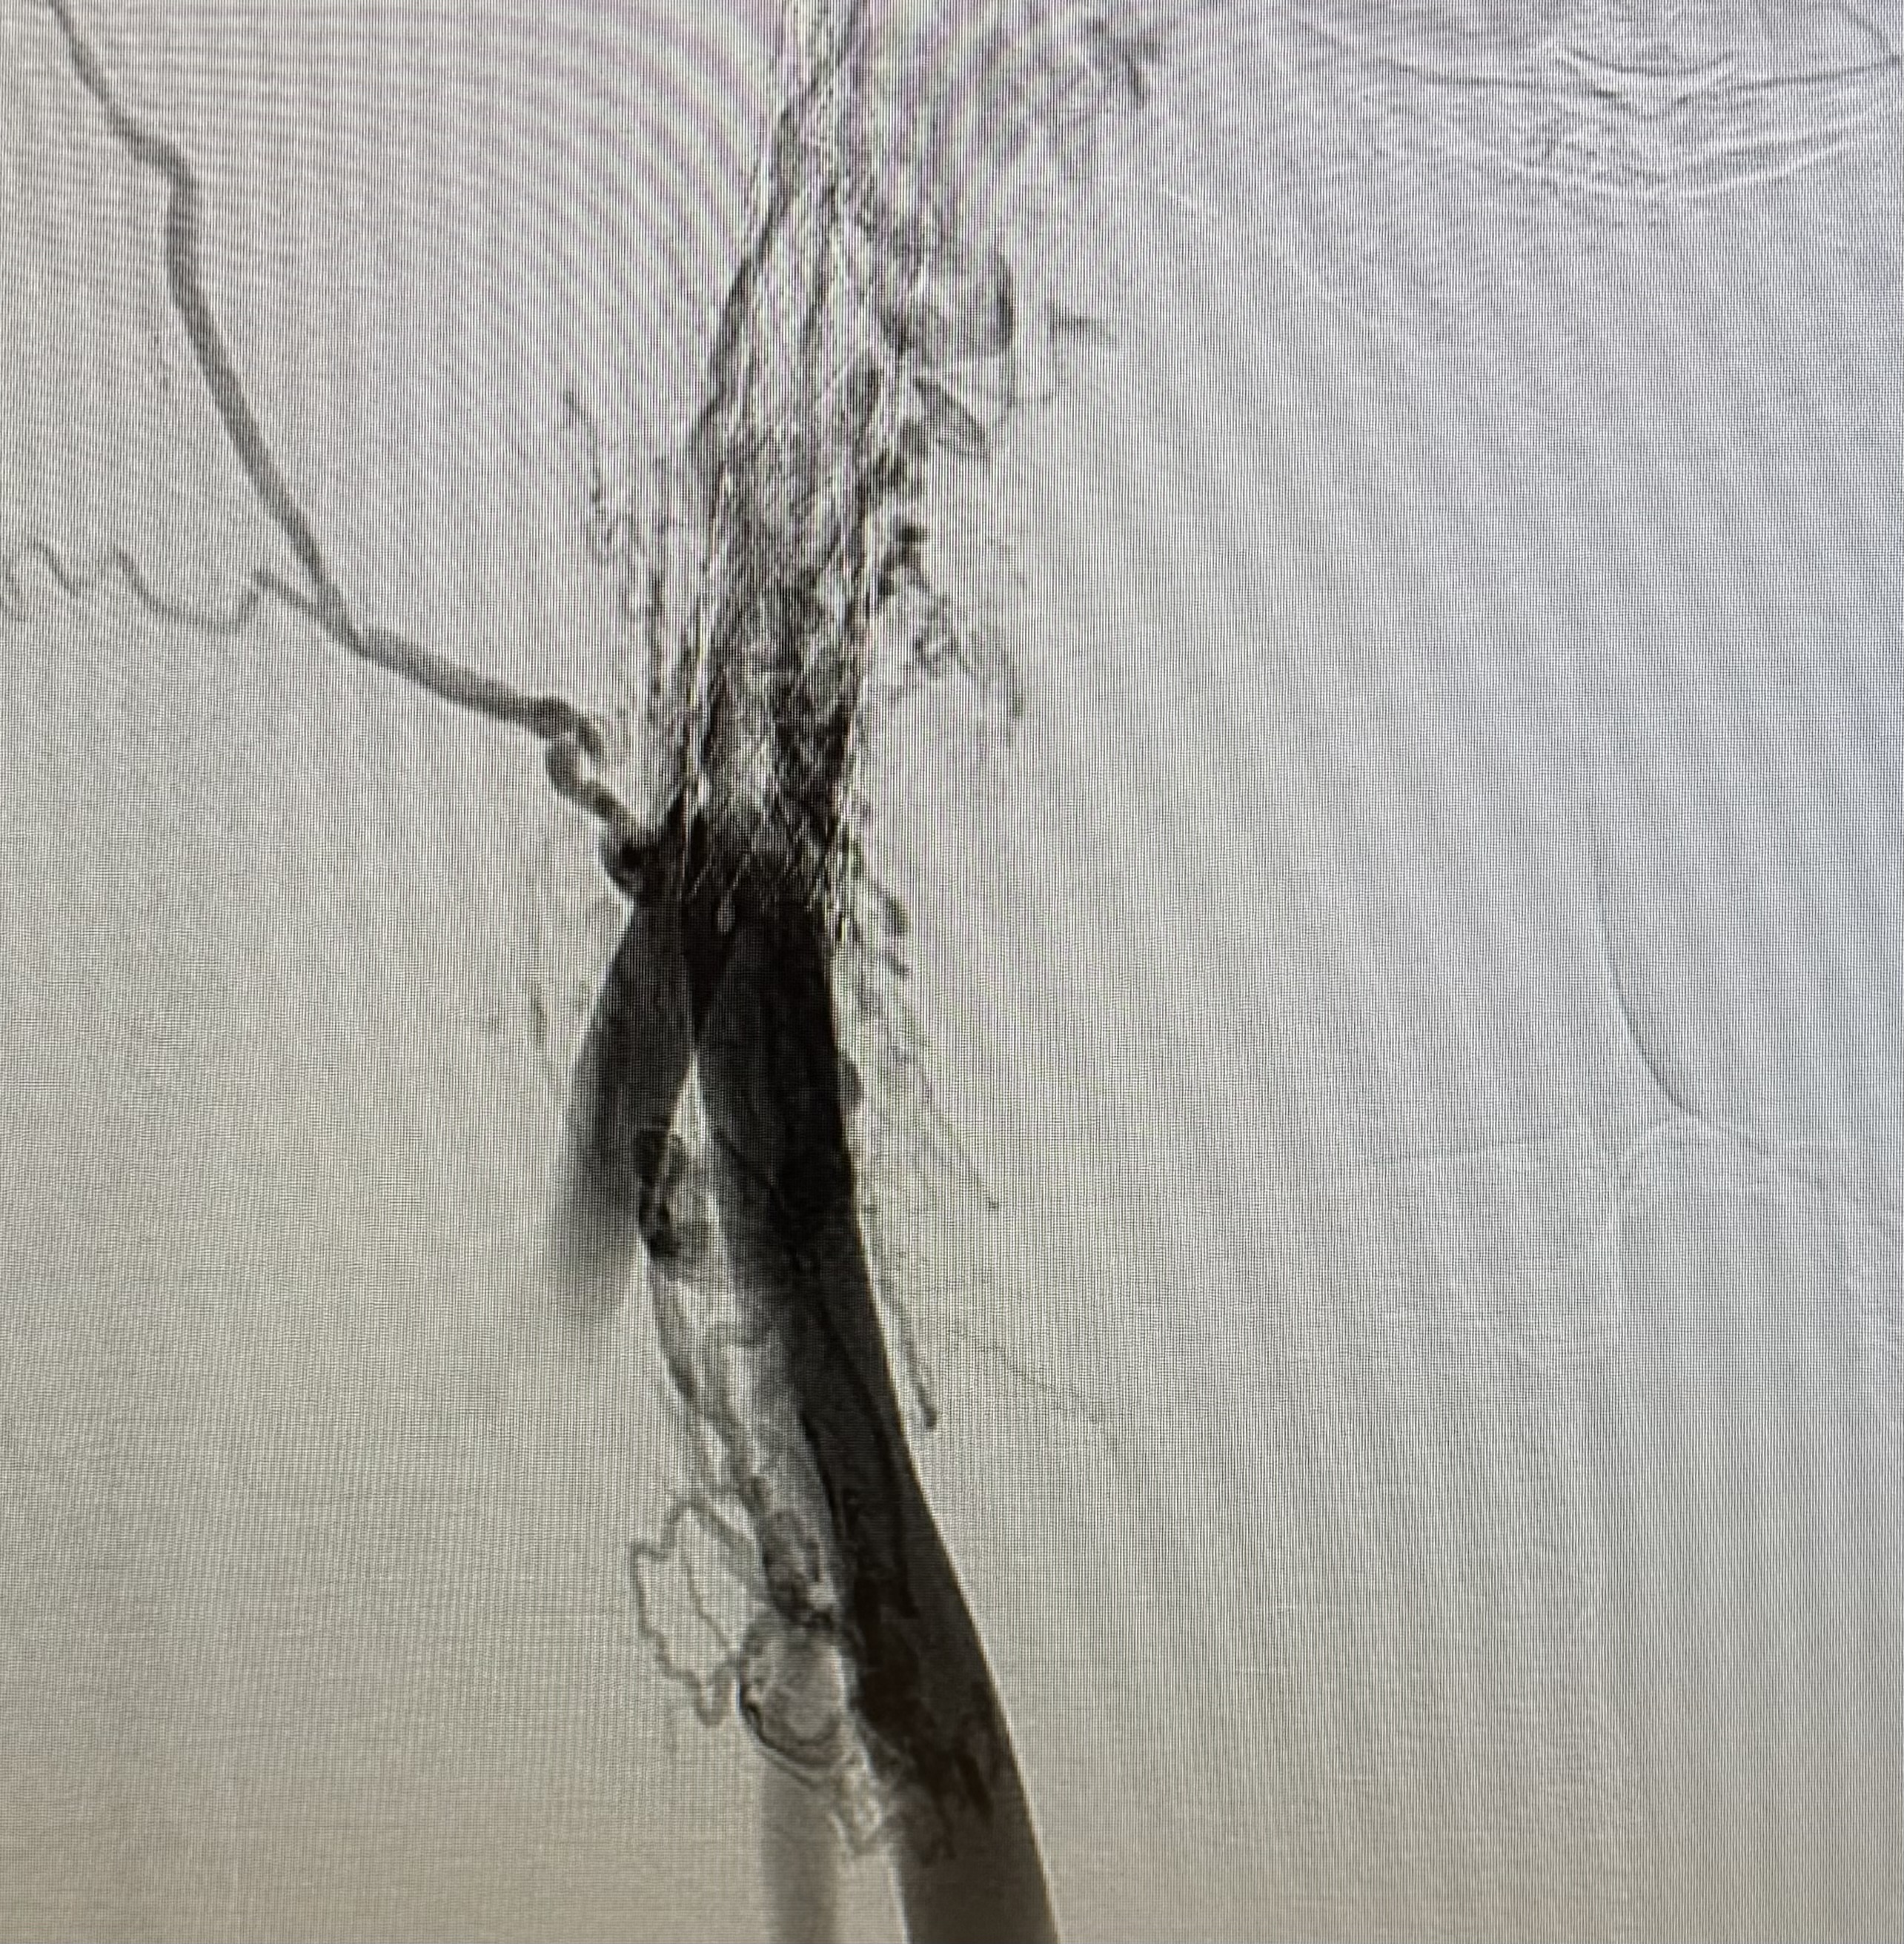

Venogram showed occluded left common iliac vein.

Accesses at right and left popliteal veins were established. A FlowTriever disc was inserted as a temporary inferior vena cava filter via the right popliteal access. Wire was passed through the thrombosed left common iliac to femoral stent. Aspiration thrombectomy was performed and aspirated small amount of chronic blood clots. Subsequent, an "up and over" access was established with a 16 French aspiration catheter inserted through the right popliteal access to the left common iliac stent. The Clottriever catheter was inserted through the left popliteal access into the aspiration catheter. The Clottriever catheter was then retrieved, with simultaneous forward movement of the aspiration catheter to protect the collection basket of the Clottriever catheter from damaging the left common iliac stent during the retrieval process. Moderate amount of blood clots were retrieved with multiple attempts. Balloon angioplasty was then performed and blood flow through the common iliac vein was restored. There was significant improvement in terms of lower limb swelling after the procedure and the patient was discharged later with anticoagulation therapy.